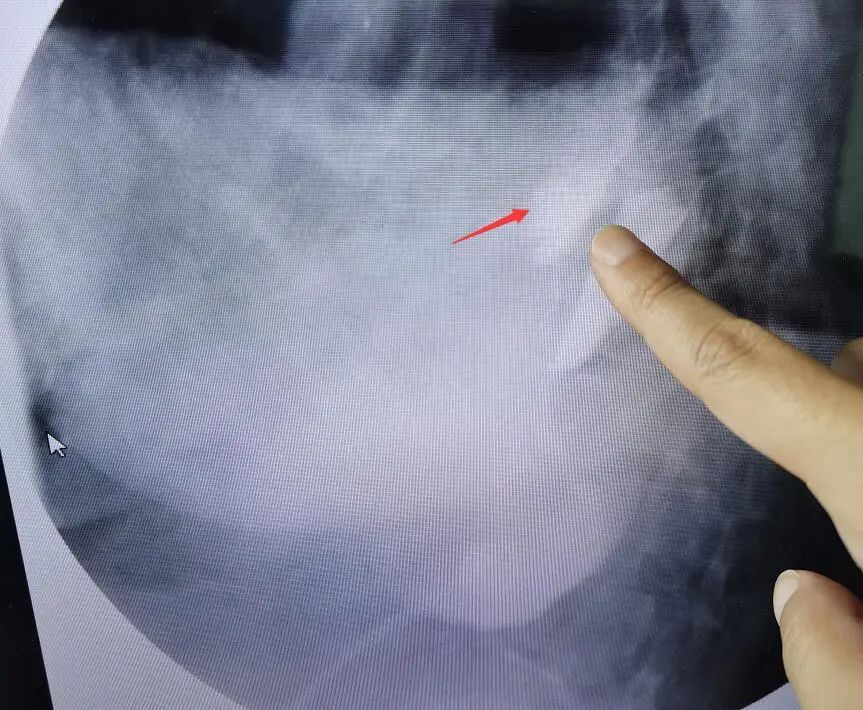

食管造影能夠清晰地看到造影劑漏入胸腔

根據(jù)自己多年的工作經(jīng)驗(yàn),瑞慈醫(yī)院副院長(zhǎng)、胸外科主任曹飛接診患者后,第一時(shí)間想到了自發(fā)性食管破裂。食管造影檢查顯示,果不其然:食管中下段破裂。